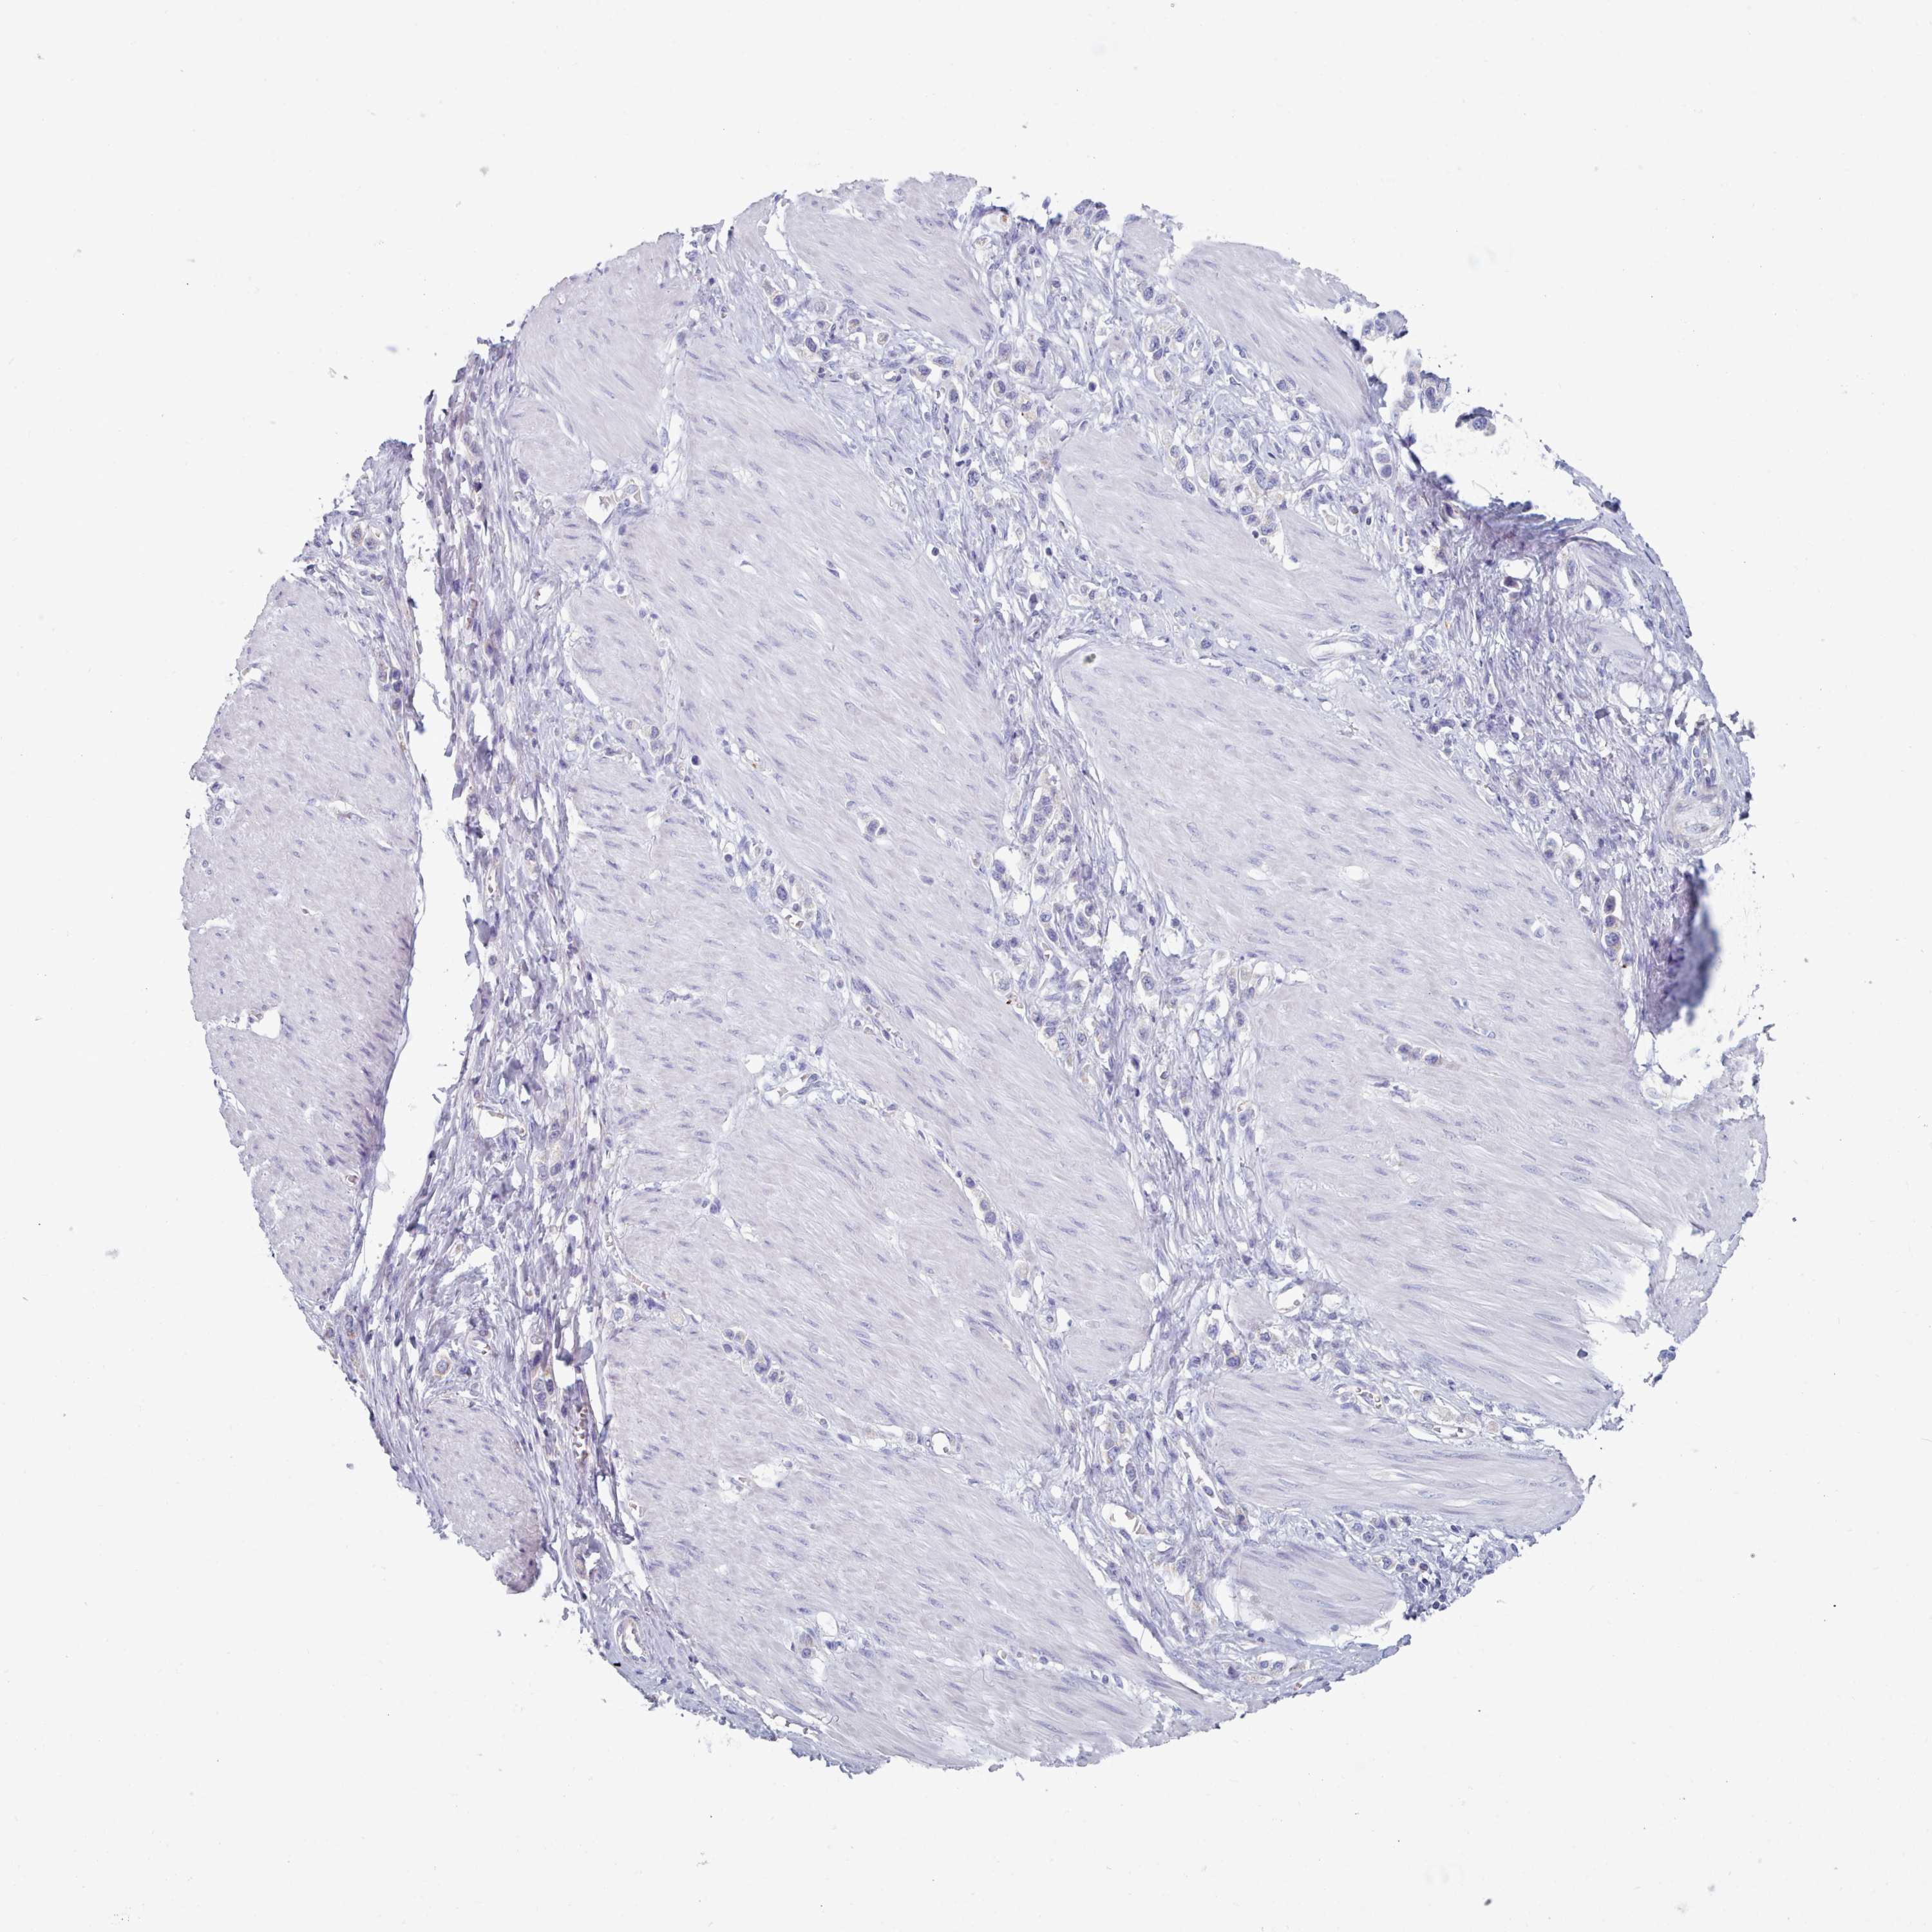

STOMACH CANCER - Protein expressioni

A mouse-over function shows sample information and annotation data. Click on an image to view it in a full screen mode. Samples can be filtered based on level of antibody staining by selecting one or several of the following categories: high, medium, low and not detected. The assay and annotation is described here.

Note that samples used for immunohistochemistry by the Human Protein Atlas do not correspond to samples in the TCGA dataset.

Antibody stainingi

Antibody staining in the annotated cell types in the current human tissue is reported as not detected, low, medium, or high, based on conventional immunohistochemistry profiling in selected tissues. This score is based on the combination of the staining intensity and fraction of stained cells.

Each image is clickable and will lead to virtual microscopy that enables deeper exploration of all samples and also displays staining intensity scores, fraction scores and subcellular localization as well as patient and tissue information for each sample.

Antibody HPA049552

Antibody HPA072442

Staining

High

Medium

Low

Not detected

Intensity

Strong

Moderate

Weak

Negative

Quantity

>75%

75%-25%

<25%

None

Location

Nuclear

Cytoplasmic/membranous

Cytoplasmic/membranous,nuclear

Adenocarcinoma, NOS

Adenocarcinoma, High grade